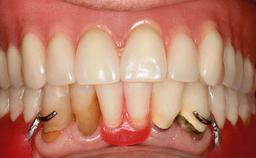

In 2007, a 97-year-old patient presented for treatment at the Geneva Dental School. His dentist had retired. Like many elderly patients, he was left without regular dental care. He lived on a geriatric ward, as he was partly dependent on help with most of the activities of daily living (ADL), such as getting dressed, washing, taking a shower, or climbing stairs. However, he was able to go to the bathroom and get up from bed on his own (ADL score 80, min. 18, max. 126; a low score signifies a high degree of dependency) (Lawton and Brody 1969). He was not bound to a wheelchair, but used a walker. Moreover, he was socially highly active—his family visited on a regular basis and he often went to the restaurant with his friend, who was some 20 years younger. His cognitive function did not seem to be impaired in a normal conversation, although his MMSE score was only 21/30 at that time (Folstein and coworkers 1975). The patient was a retired pharmacist, and his latest passion was astronomy.